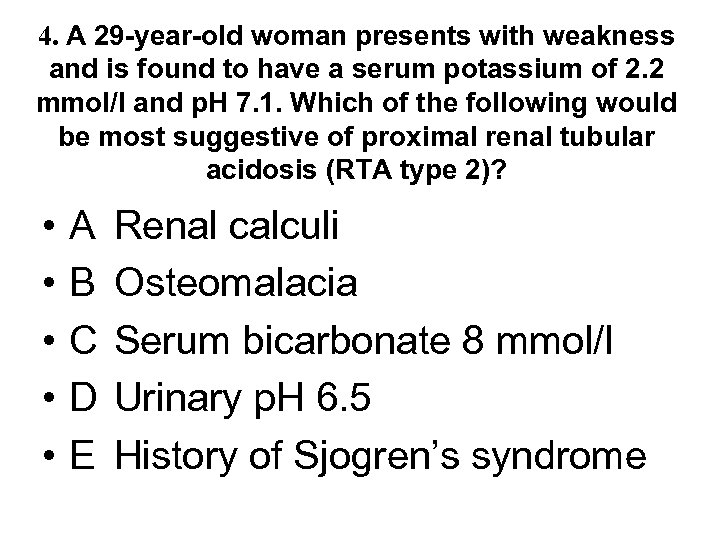

4. A 29 -year-old woman presents with weakness and is found to have a serum potassium of 2. 2 mmol/l and p. H 7. 1. Which of the following would be most suggestive of proximal renal tubular acidosis (RTA type 2)? • • • A B C D E Renal calculi Osteomalacia Serum bicarbonate 8 mmol/l Urinary p. H 6. 5 History of Sjogren’s syndrome

4. A 29 -year-old woman presents with weakness and is found to have a serum potassium of 2. 2 mmol/l and p. H 7. 1. Which of the following would be most suggestive of proximal renal tubular acidosis (RTA type 2)? • • • A B C D E Renal calculi Osteomalacia Serum bicarbonate 8 mmol/l Urinary p. H 6. 5 History of Sjogren’s syndrome

4. A 29 -year-old woman presents with weakness and is found to have a serum potassium of 2. 2 mmol/l and p. H 7. 1. Which of the following would be most suggestive of proximal renal tubular acidosis (RTA type 2)? • • • A B C D E Renal calculi Osteomalacia Serum bicarbonate 8 mmol/l Urinary p. H 6. 5 History of Sjogren’s syndrome

4. A 29 -year-old woman presents with weakness and is found to have a serum potassium of 2. 2 mmol/l and p. H 7. 1. Which of the following would be most suggestive of proximal renal tubular acidosis (RTA type 2)? • • • A B C D E Renal calculi Osteomalacia Serum bicarbonate 8 mmol/l Urinary p. H 6. 5 History of Sjogren’s syndrome

What can go wrong? Type 2 - Proximal RTA due to failure of bicarbonate reabsorption (uncommon in adults) Type 1 - Distal RTA due to failure of acid secretion (common) Type 3 - Poorly characterised mix of types 1 and 2 (vanishingly rare) Type 4 - Hyporeninaemic hypoaldosteronism causing acidosis and hyperkalaemia (common)

What can go wrong? Type 2 - Proximal RTA due to failure of bicarbonate reabsorption (uncommon in adults) Type 1 - Distal RTA due to failure of acid secretion (common) Type 3 - Poorly characterised mix of types 1 and 2 (vanishingly rare) Type 4 - Hyporeninaemic hypoaldosteronism causing acidosis and hyperkalaemia (common)

Renal tubular acidosis • Distal - type 1 • Proximal - type 2 • rare Frequency • common Mechanism • failure to excrete H+ • failure to reabsorb bicarbonate • 1 y or 2 y to cystinosis, • 1 y or 2 y to SLE, Causes wilsons, myeloma, sjogrens, PBC, sjogrens - often assoc CAH, urinary with failure to reabsorb obstruction, PO 4, AA, glucose, urate medullary sponge, (fanconi) lithium

Renal tubular acidosis • Distal - type 1 • Proximal - type 2 • rare Frequency • common Mechanism • failure to excrete H+ • failure to reabsorb bicarbonate • 1 y or 2 y to cystinosis, • 1 y or 2 y to SLE, Causes wilsons, myeloma, sjogrens, PBC, sjogrens - often assoc CAH, urinary with failure to reabsorb obstruction, PO 4, AA, glucose, urate medullary sponge, (fanconi) lithium

Renal tubular acidosis • Distal - type 1 Urine p. H • • Serum bic • Serum K Complications • Therapy p. H > 5. 5 often < 10 mmol/l usually low nephrocalcinosis, stones • low dose bicarbonate, K supps, citrate to stop Ca-PO 4 deposition if stone former

Renal tubular acidosis • Distal - type 1 Urine p. H • • Serum bic • Serum K Complications • Therapy p. H > 5. 5 often < 10 mmol/l usually low nephrocalcinosis, stones • low dose bicarbonate, K supps, citrate to stop Ca-PO 4 deposition if stone former

Renal tubular acidosis • Distal - type 1 Urine p. H • • Serum bic • Serum K Complications • Therapy • Proximal - type 2 p. H > 5. 5 • often < 10 mmol/l • usually low • nephrocalcinosis, • stones • low dose bicarbonate, • K supps, citrate to stop Ca-PO 4 deposition if stone former Variable* 14 -20 mmol/l* normal or low osteomalacia, rickets (not calcinosis or stones) high dose bicarbonate *when serum bicarb drops below a threshold level in type 2 RTA, the tubules start reabsorbing bicarbonate which means serum bic can be higher and urine p. H lower than in type 1 - known as the “threshold effect”